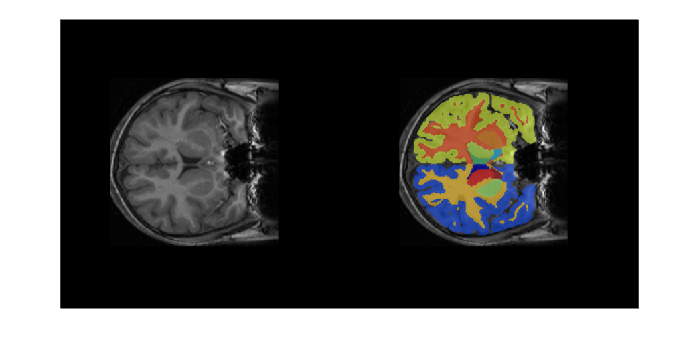

Overlay a slice from the predicted segmentation map on a corresponding slice from the input volume using the labeloverlay function. Include all the brain structure labels except the background label.

sliceIdx = 80;

testSlice = rescale(vol(:,:,sliceIdx));

predSegMap = predictedSegMaps(:,:,sliceIdx);

B = labeloverlay(testSlice,predSegMap,"IncludedLabels",2:32);

figure

montage({testSlice,B})